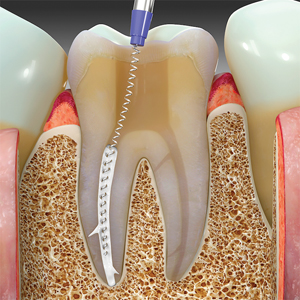

Bioceramic Dispersion Root Filling: Revision of Legacy Obturation Protocols

Serota Fig 7 alternate text for this image

Despite the fact that degradation and dissolution of gutta-percha (GP) and sealer (SE) jeopardize positive treatment outcomes, these legacy materials are still used in diverse protocols for root filling canals. 1 This paper reviews the historical cognitive dissonance in endodontics; the biochemical seal created by GP and SE diminishes over time with negative sequelae and … Read more